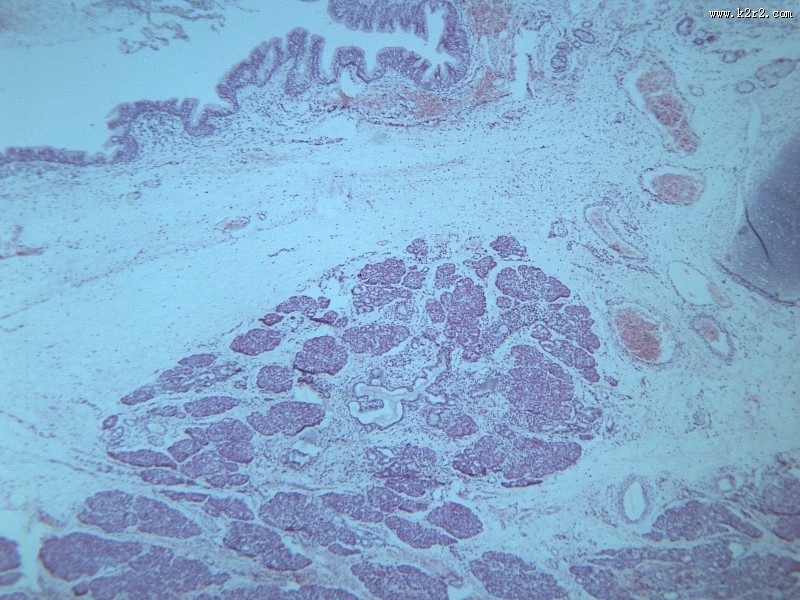

首页 > 其他类别 > 畸胎瘤(12张) > 畸胎瘤 第9张

畸胎瘤 - 第9张